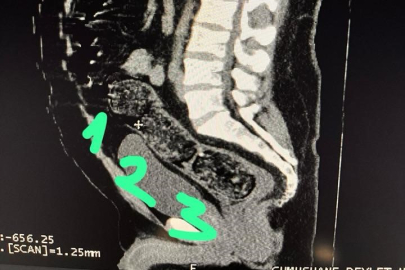

Adli makamların talimatı üzerine Gümüşhane Devlet Hastanesine götürülen şahsa yönelik iç beden muayenesinde bağırsaklarında 3 adet kapsül olduğu tespit edildi. Hastanede yapılan müdahalenin ardından şahsın bağırsaklarından çıkarılan kapsüllerin içerisinde toplamda 271,55 gram metamfetamin ele geçirildi.